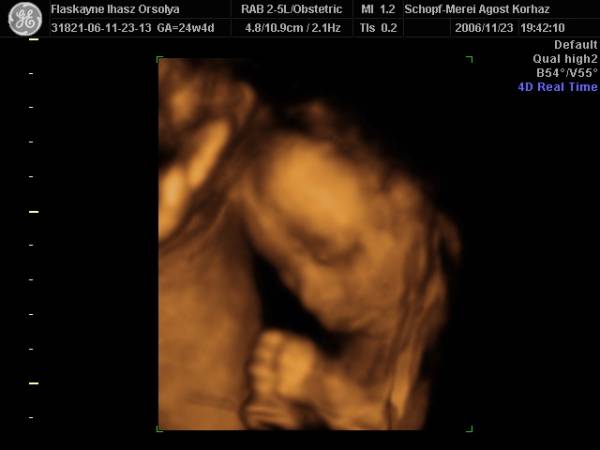

27.héten(Nagyon sokat változott,husis)